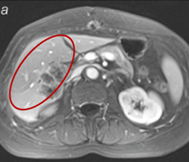

MRI pred terapijo

MRI 30 dni po začetku terapije